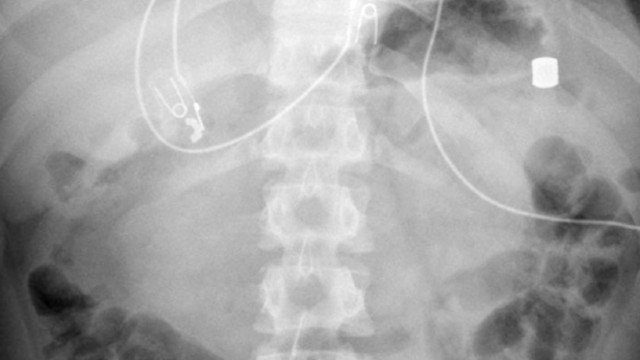

Um adolescente de 13 anos deu entrada nas urgências de um hospital nos Estados Unidos com fortes dores abdominais. Após uma série de exames, os médicos descobriram que ele tinha 21 ímãs no estômago e intestinos.

De acordo com o site BMJ Case Reports, o paciente tinha “múltiplos corpos estranhos metálicos” no estômago e cólon, com diâmetros de cerca de 8 milímetros.

Para ser submetido a mais exames, o jovem foi transportado para outro hospital, onde novas radiografias confirmaram que se tratava de ímãs de neodímio.

A ingestão dos objetos magnéticos criou uma úlcera gástrica “muito dolorosa” ao adolescente, assim como uma perfuração do intestino. A perfuração poderia ter sido ainda mais grave e até mesmo levar à morte do jovem.